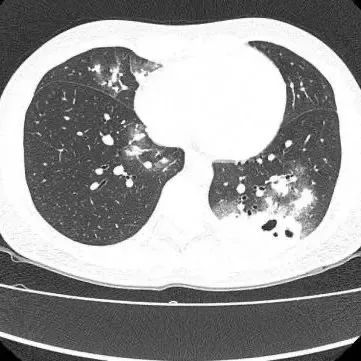

胸部CT显示其双肺多发感染

伴多发空洞形成

在影像学表现方面,典型CT表现是单发/多发结节伴“晕轮征”,结节液化坏死可形成空洞形似“鬼脸征”,空洞常为薄壁空洞、无液平。